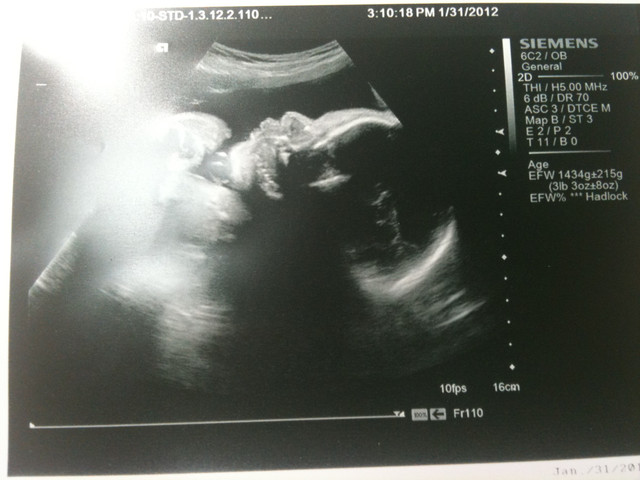

醫生說你就 1.4 公斤啦

這次醫生給了我們你的2D寫真

真的好久沒有拿到相片了

看到你挺挺的鼻子

下面這張相片 醫生說你在吃手 是有點餓嗎